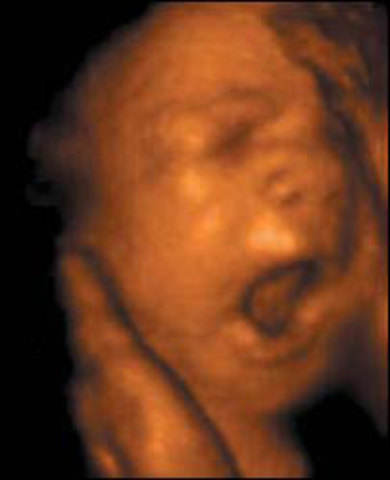

• 24 SEMANA

24 SEMANA

El feto mide 30cm. y pesa entre 700 gramos y 1Kg.La cara tiene las características de un niño. La piel aparece arrugada, porque creció más rápido que el tejido subcutáneo. Tiene color rojizo porque deja traslucir el color de los músculos y de la sangre que circula por los capilares superficiales. Se cae el lanugo. Aparecen las pestañas en ambos párpados.